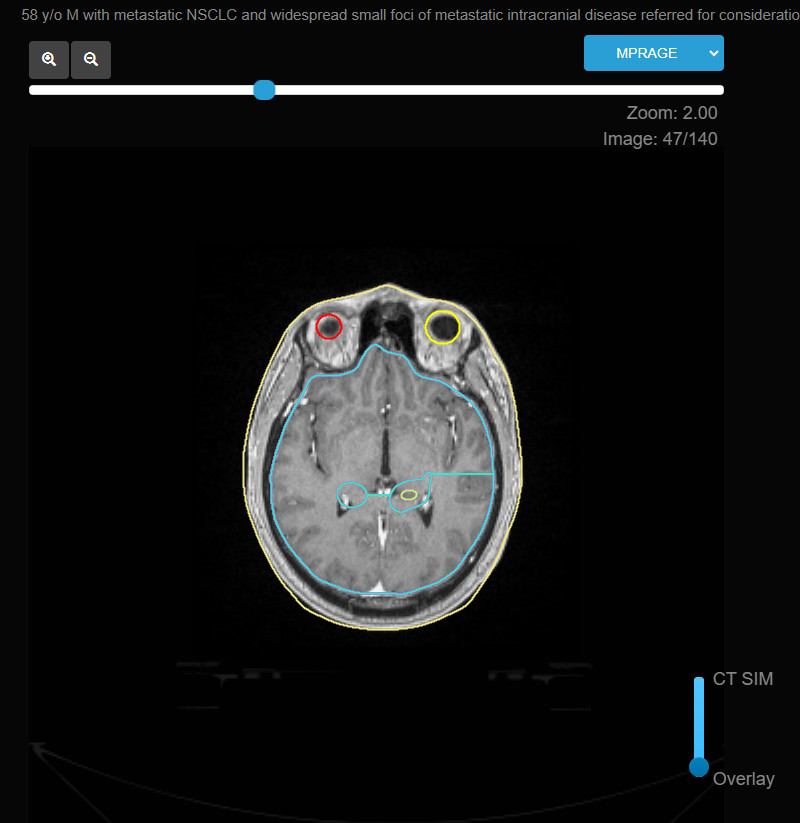

Brain metastasis is a common and serious complication in patients with advanced cancer, particularly those with lung, breast, melanoma, and renal cell cancers. Radiation therapy plays a central role in the management of brain metastases, aiming to control the disease, alleviate symptoms, and improve quality of life.

- Stereotactic Radiosurgery (SRS): SRS is typically used for patients with a limited number of brain metastases (commonly 1-4 lesions). It delivers a high dose of radiation to the tumor with minimal impact on surrounding healthy tissue. It is also considered for patients with surgically resected brain metastases to prevent local recurrence.

- Stereotactic Radiosurgery (SRS): SRS targets only the tumor and a small margin around it, sparing the surrounding healthy brain tissue. It is highly focused, allowing for high doses to be delivered to the tumor while minimizing damage to other parts of the brain.

- Stereotactic Radiosurgery (SRS): SRS is delivered using specialized equipment such as a Gamma Knife, CyberKnife, or linear accelerators with SRS capabilities. This technique is highly precise, requiring advanced imaging to accurately locate the metastases.

- Image-Guided Radiation Therapy (IGRT): IGRT is often used in conjunction with SRS to enhance the accuracy of radiation delivery, particularly for small or deep-seated metastases.

- Imaging: Follow-up imaging with MRI or CT scans is essential to assess treatment response and monitor for any recurrence or progression of brain metastases.